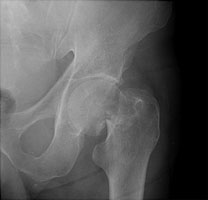

Femoral neck fractures also result from falls, especially in elderly and osteoporotic females. They are associated with radial and humeral fractures. The Garden classification is widely used to categorize these fractures. Garden I is an incomplete fracture through the femoral neck while with Garden II, the fracture is complete. With Garden III fractures, there is impaction, and with Garden IV, the femoral neck is superiorly migrated relative to the femoral head. Garden IV fractures have the highest risk of avascular necrosis.

B | Lateral view of a Garden II fracture. |